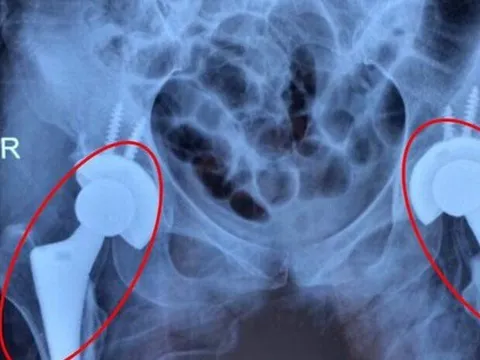

Nhiều người trẻ bị mục xương vì chất kích thích ai cũng dùng